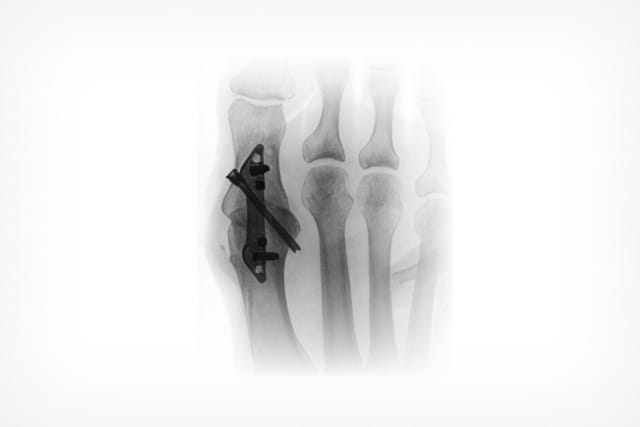

SpeedMTP®

Rapid Compression Implant

Speed and compression of a staple, stability of a titanium locking plate.*

The SpeedMTP® System is engineered for performance — delivering rapid, precise placement, powerful dynamic compression, and an ultra-low-profile designed to reduce soft tissue irritation without compromising strength or stability.

The SpeedMTP® System

- Low profile: 1.3mm thickness

- Rounded edges designed to reduce soft tissue irritation

- Screws angulated at 2.5° for additional plane stability and bicortical fixation